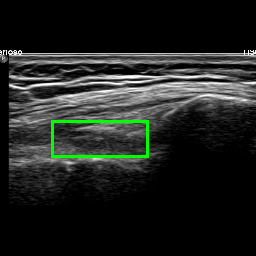

Figure 9 shows four examples of images that are more challenging to classify even by medical experts. This usually happens when there is noise in the US scan (as in Figure 9c) or when the SQR is borderline between Distended and Non-distended (as in Figure 9d). Figure 9a is correctly classified by both approaches as Non-distended. Figure 9b is correctly classified by the Multi-task approach but not by the Detection approach. Vice versa, Figure 9c is correctly classified by the Detection approach and not by the Multi-task approach. Finally, both solutions wrongly classify Figure 9d.

Refer to caption

(a) Non-distended SQR

(b) Distended SQR

(c) Non-distended SQR

(d) Distended SQR

Figure 9: Examples of images that are intuitively hard to classify.